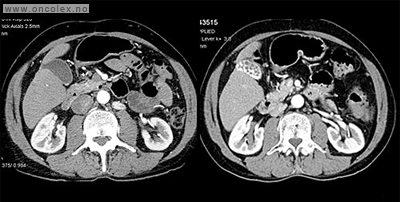

Kombinasjonen synes å ha god virkning på nevroendokine svulster med KI-67 over 10–15%, av og til også ved sulter med lavere KI-67%. Kuren brukes også ved nevroendokrine karcinomer med ikke for høy Ki-67%, Fordelen med denne kombinasjonen er at den er lite skadelig for nyrene og gis som tabletter som pasienten kan ta hjemme. Behandlingskontroll gjøres vanligvis med CT, hver 3. måned.

Kuren gis som en 5-dagers behandling, etterfulgt av 1-dags behandlinger hver 3. (–4.) uke. Behandlingskontroll gjøres vanligvis med CT, hver 3. måned. Ved effekt over 1 år forlenges mellomrommet mellom 1-dags behandlingene opptil 6 uker.

Bildeeksempler